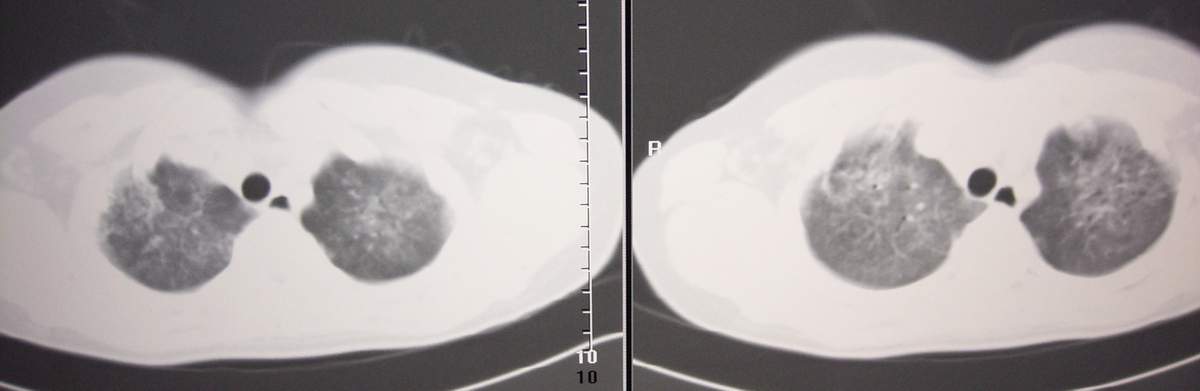

标题: CT7371:[讨论]肺部病变!

女,咳嗽、气喘2月余。

两肺弥漫性病变,考虑:1。肺水肿。2。肺蛋白沉积症。

双肺纹理增多,紊乱,呈网格状,期间搀杂斑片及磨玻璃样阴影.考虑;感染性病变_首先考虑:特殊感染:嗜酸性肺病.

双肺弥漫性病变, 冠状重建肺血管增粗,建议继续上传详细临床资料,x线片

双肺弥漫磨玻璃样影,边界不清,似蝶翼征。肺纹理增多。

考虑:肺泡蛋白沉积症。建议临床进一步检查。